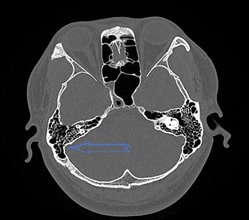

正常乙状窦 乙状窦前位+乙状窦憩室

在正常的CT图像上耳蜗基底转的层面是看不颈静脉球的;当颈静脉球顶部超过耳蜗基底圈下缘或鼓室下缘,或突入中耳腔时,称为高位。

乙状窦前位+乙状窦憩室+颈静脉球高位(黄色箭头)

总之,耳朵里出现了类似心跳的声音时,千万不要掉以轻心。一定要及时就医,进行全面的检查和诊断,以便早期发现病因,采取有效的治疗措施,避免病情延误和加重。特别是乙状窦前位及颈静脉球高位,认识到它的影像特点,尤其是颞骨高分辨CT扫描通过多平面的重建图像,很容易精确诊断,清楚地了解乙状窦的形态,看看有没有憩室,憩室大小如何,局部骨质的状况,以及有没有合并颈静脉球高位,有助于帮助临床医生了解部分搏动性耳鸣患者的发病原因,采取有效的治疗手段。